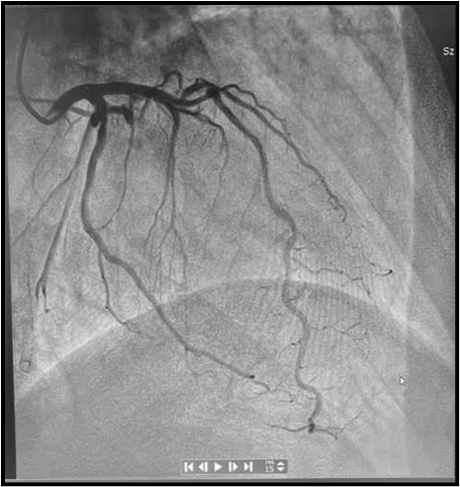

A 47-year-old man was urgently admitted on August 1, 2024 to the Cardiac Surgery Department of the 10th Military Clinical Hospital from a Specialized Hospital in the province for cardiac treatment of a left ventricular pseudoaneurysm. Coexisting hypertension and hypercholesterolemia. Previously diagnosed and treated at the aforementioned Specialized Hospital. He suffered a NSTEMI myocardial infarction on 8/05/2024. - Coronary angiography showed bivascular disease - coronary angioplasty of the marginal branch infarct artery (OMCx) was performed (Figure 1).

Figure 1: Coronary angiogram after primary PCI OMCx before surgery treatment